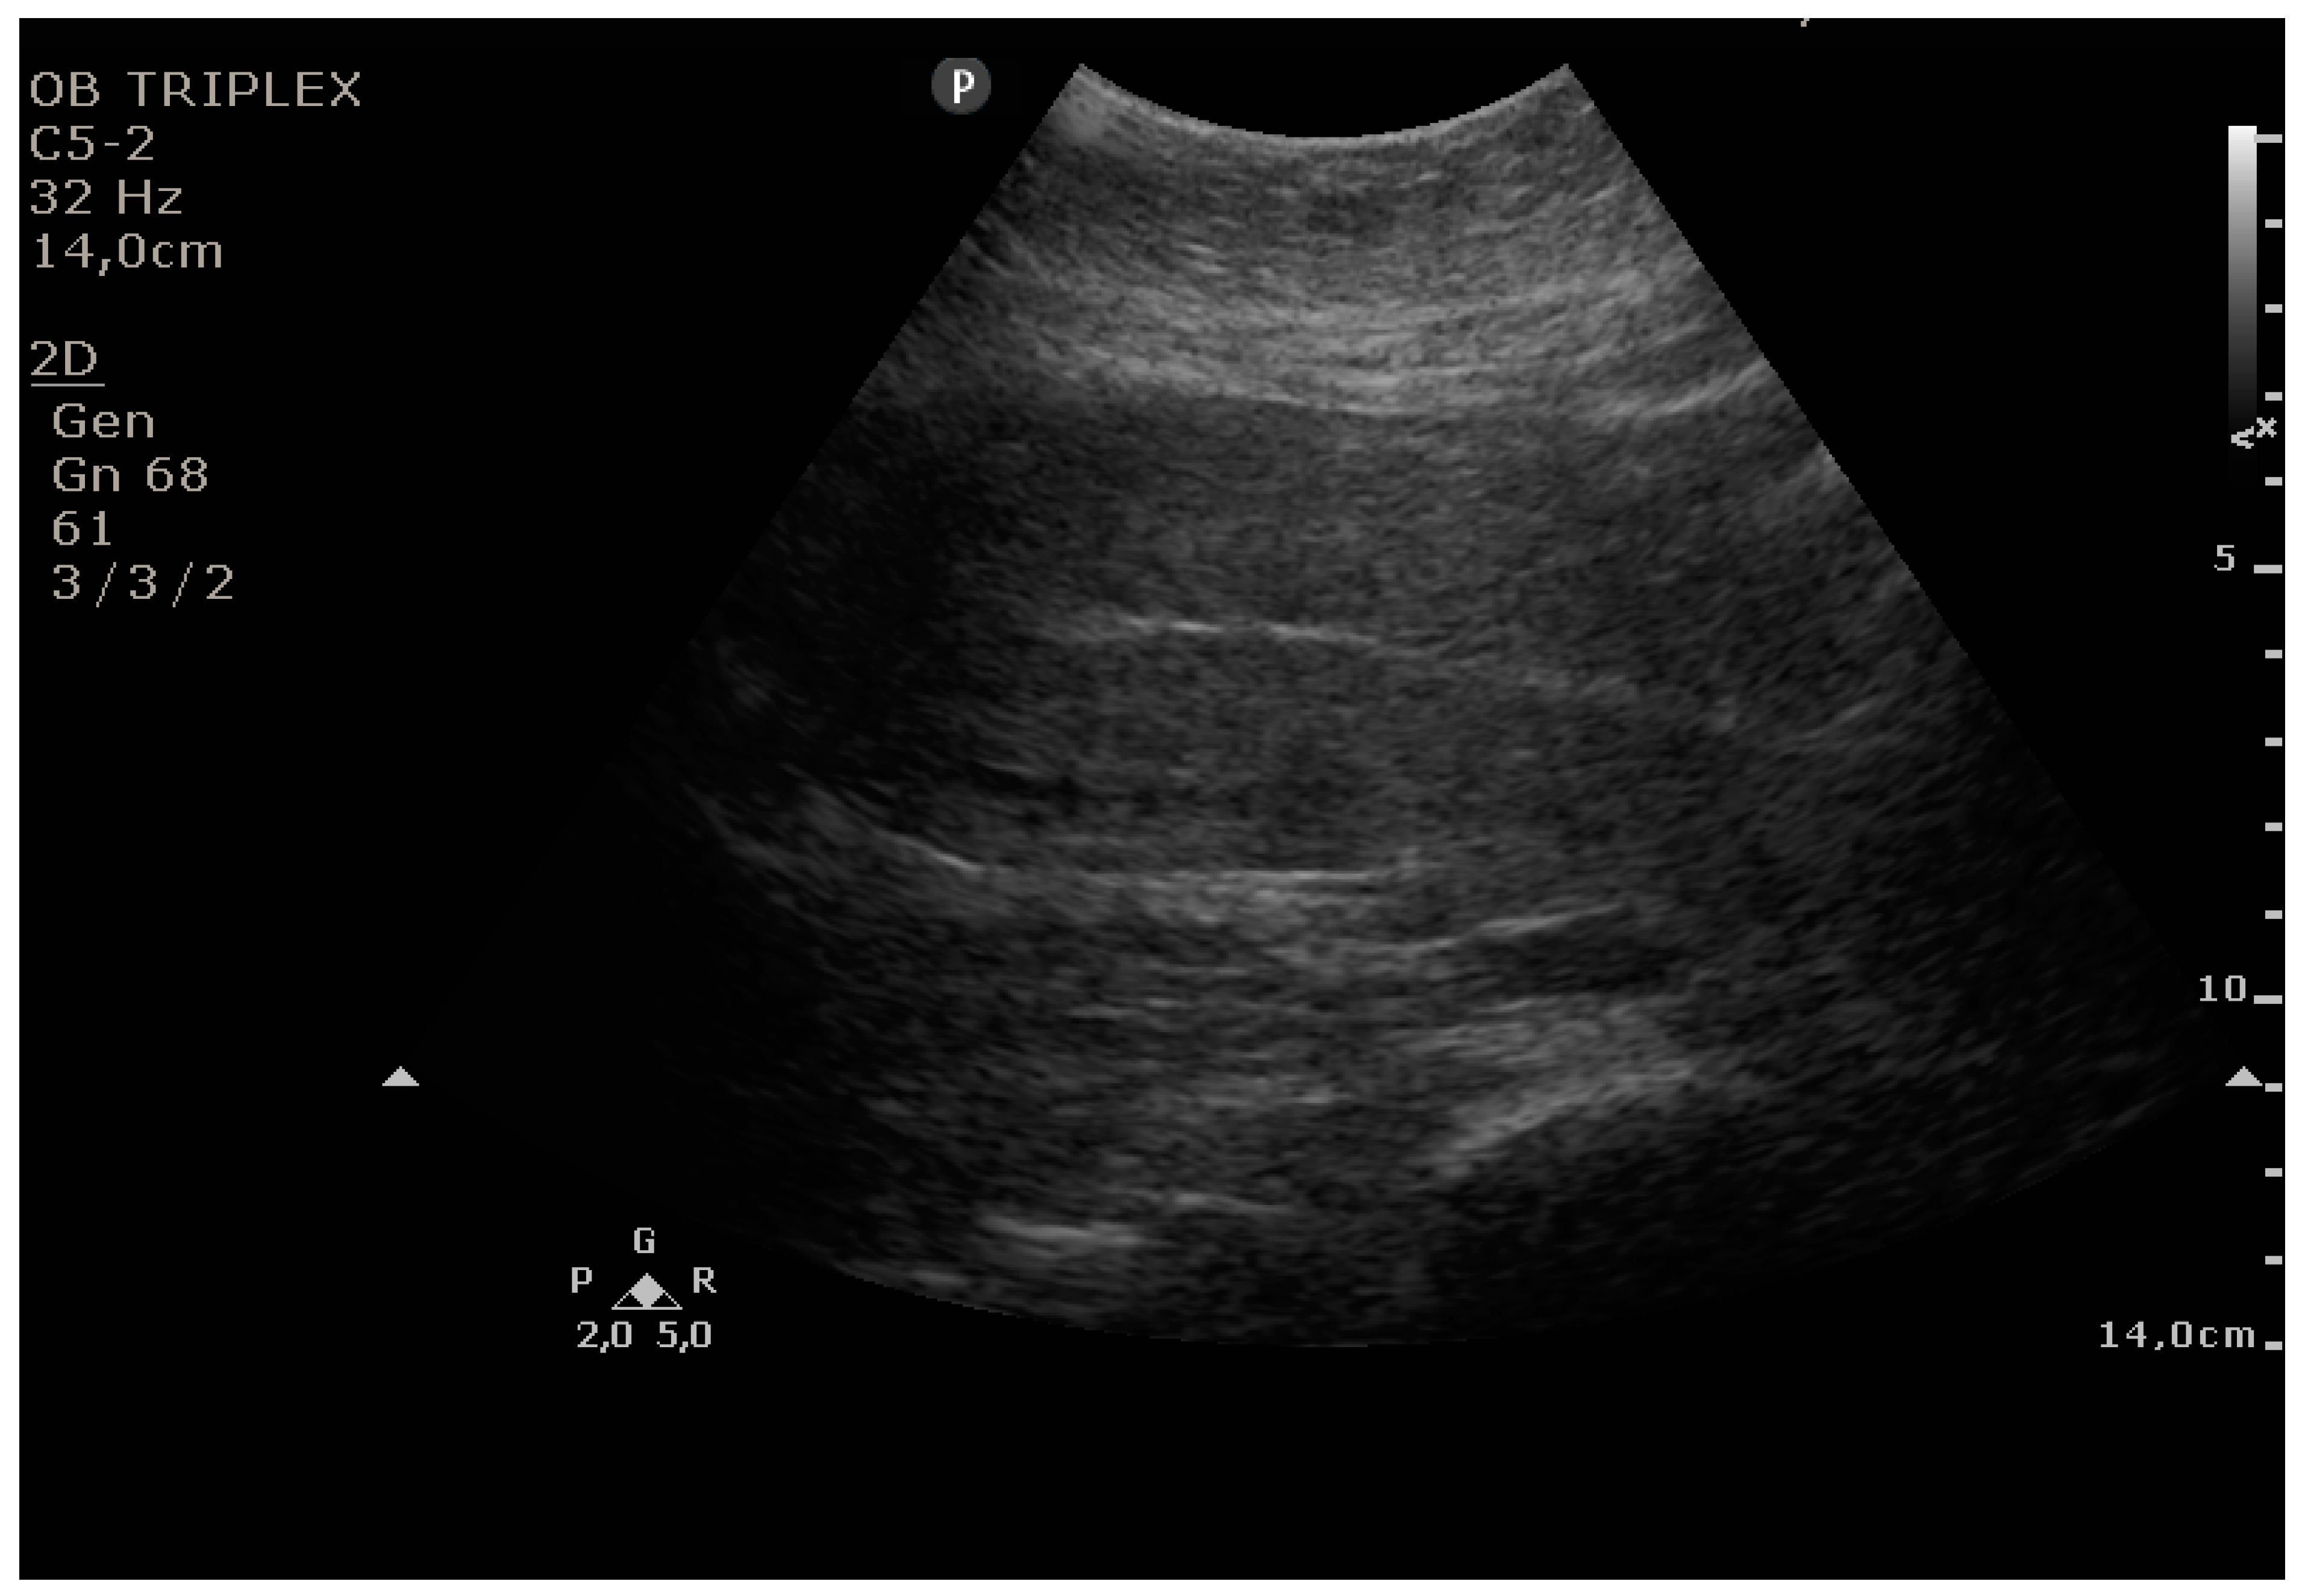

The PUUS method evaluates the proportion of the endometrial length occupied by blood or debris, as follows (Figure 1, Figure 2, Figure 3, Figure 4 and Figure 5):

Figure 1.

Grade 0: no blood or debris in the uterine cavity.